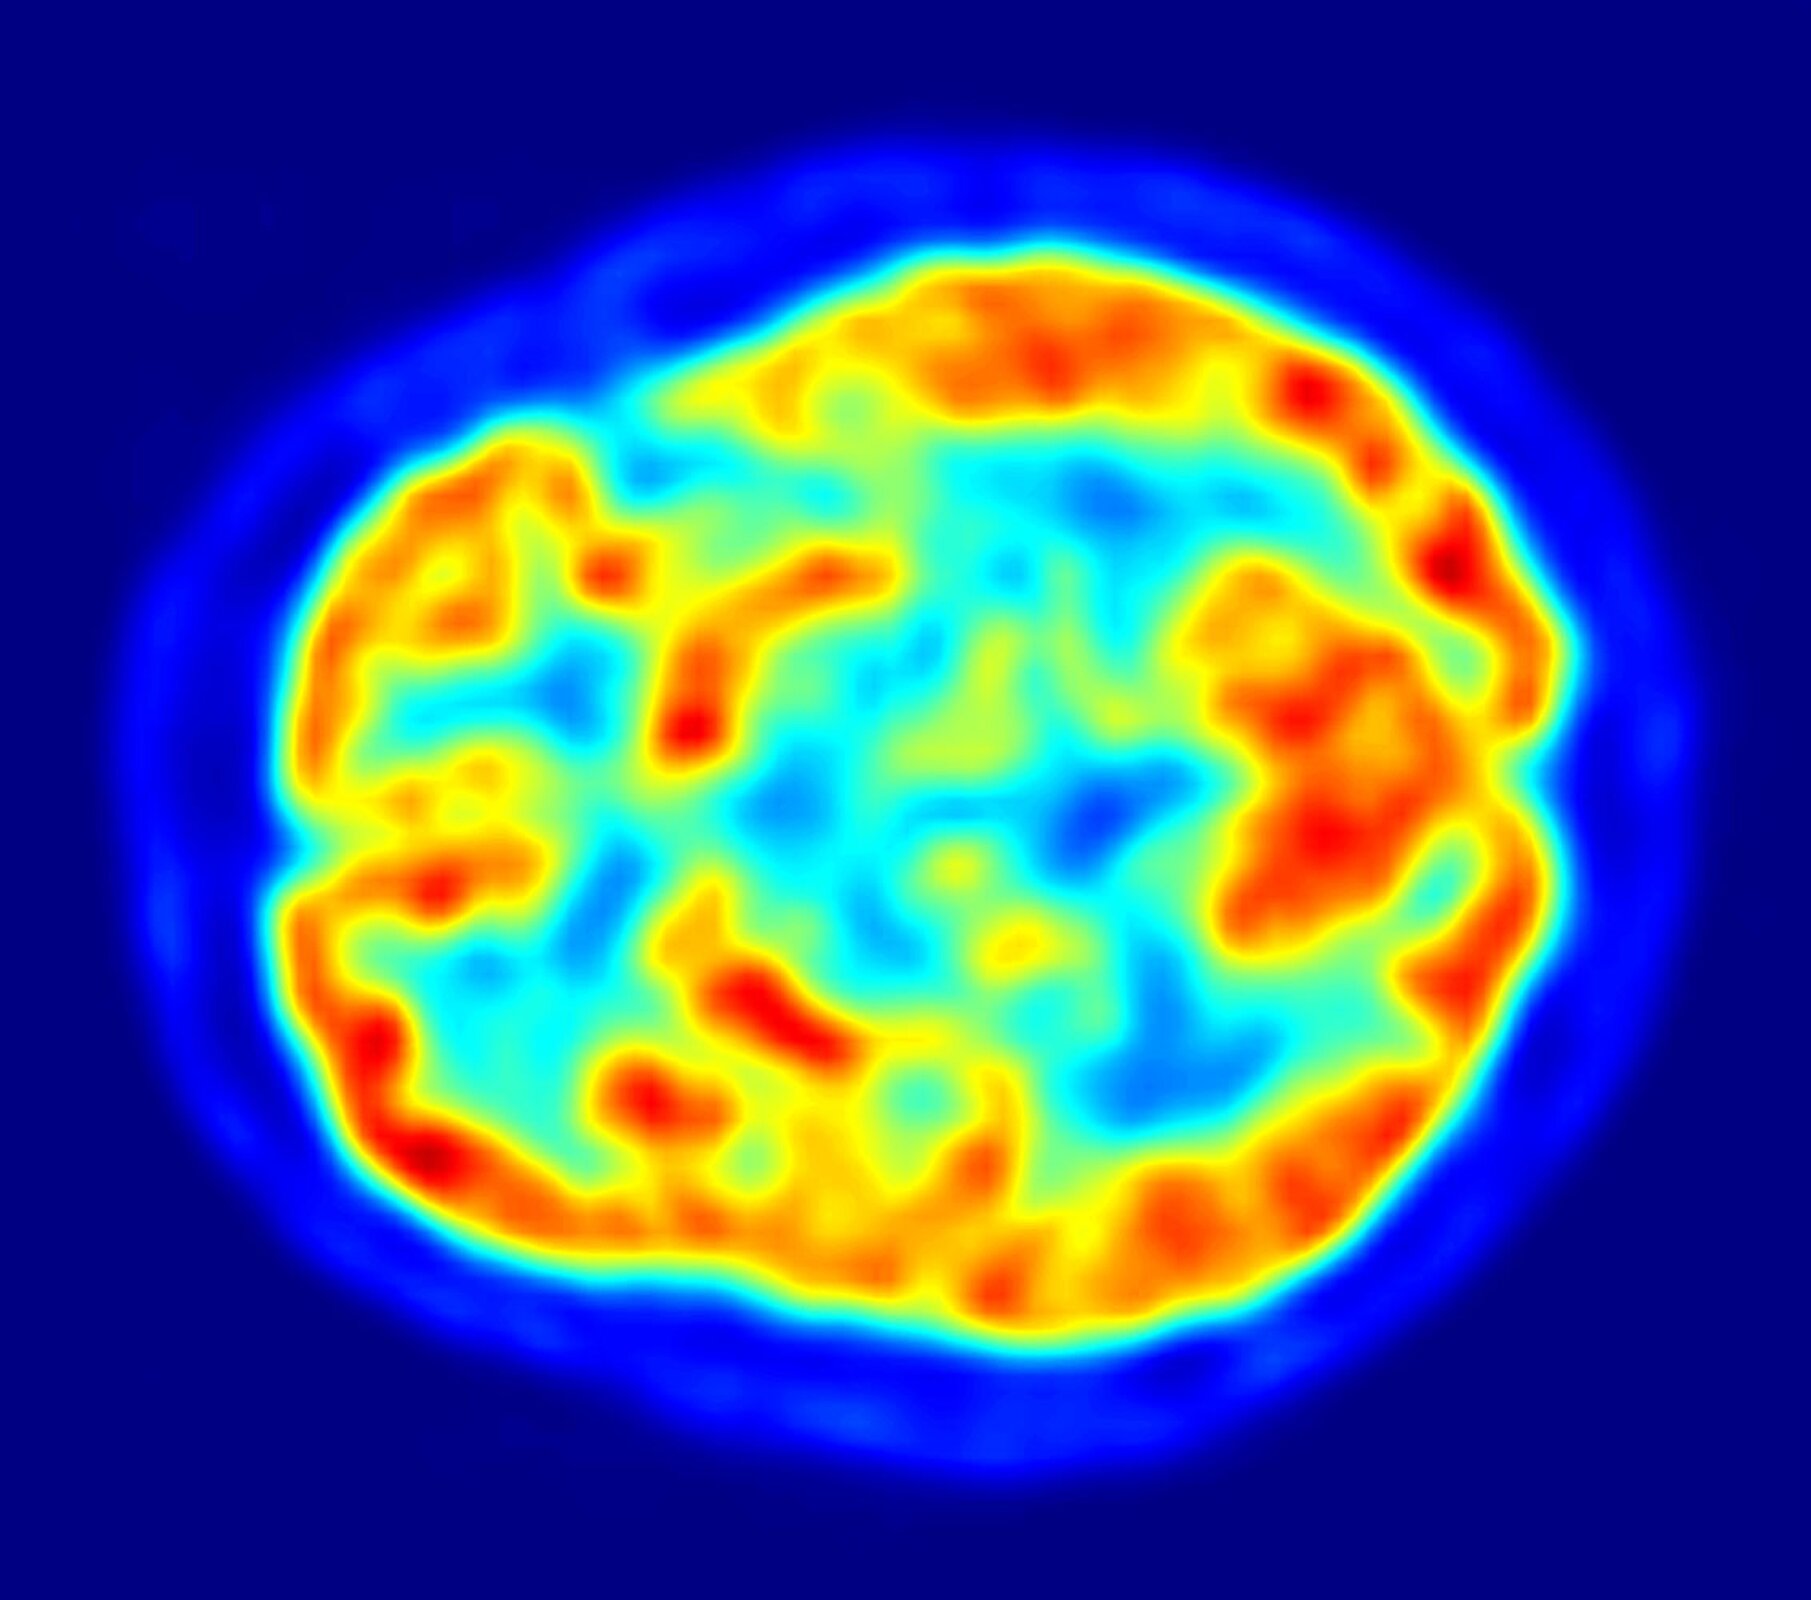

Związek ten jest pochodną glukozy, w której jedna grupa hydroksylowa została zastąpiona izotopem fluoru‑18. Ze względu na to, że obie cząsteczki są do siebie bardzo podobne, zmodyfikowana cząsteczka cukru może bez problemu wnikać do wnętrza komórek. Ma to ogromne znaczenie w wykrywaniu nowotworów. Komórki nowotworowe namnażają się niezwykle intensywnie, w wyniku czego potrzebują dużo energii, która jest dostarczana przez cząsteczki cukru. Emitowane przez cząsteczki zmodyfikowanego cukru promieniowanie pozytonowe jest wykorzystywane w technice diagnostycznej PETPET (pozytonowa tomografia emisyjna) do obrazowania czy badania funkcjonowania tkanek.

(ang. Positon Emission Tomography) tomografia emisyjna pozytonowa; metoda pozwalająca uzyskać dwuwymiarowy obraz przekroju obiektu trójwymiarowego z zastosowaniem emisji pozytonów